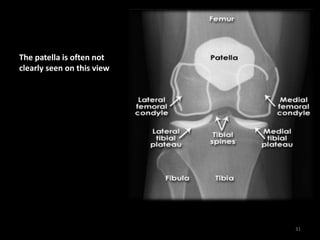

Knee - Normal AP

30

The patella is often not

clearly seen on this view